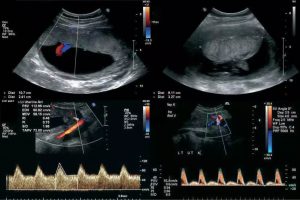

Diplomados en Ultrasonografía